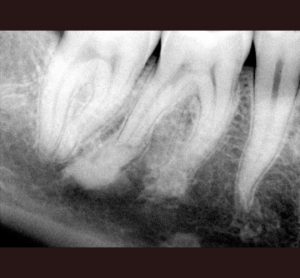

AllAccess Design and ClosureApexificationCBCT DiagnosisCracked TeethCrown Build-upEndodontic MicrosurgeryEndodontic RetreatmentEndodonticsImplantsInternal BleachingMB RootResorption Repair Endodontic Treatment: Case #1- Patient referred due to pain after recent crown cementation. Endodontic Treatment: Case #2 -Patient referred due to pain in her upper first pre molar tooth # 4 Endodontic Treatment: Case #3 – Patient referred due to pain to biting. The amalgam filling was done many years ago. Endodontic Treatment: Case #4 – Patient presented for root canal therapy referred to our office due to complex root anatomy. Endodontic Treatment: Case #5 – Necrotic (dead nerve) tooth with biting pain. Endodontic Treatment: Case #6- Necrotic (dead nerve) tooth with no pain referred for treatment. Endodontic Treatment: Case #7- Very unique tooth with lots of canals (this was a dentists tooth!) Endodontic Treatment: Case #8 – recently prepared for a crown. The patient has cold sensitivity and was referred for treatment. Endodontic Treatment: Case #9- Interesting root anatomy and diagnosis. Endodontic Treatment: Case #10 – 4 canalled lower first molar with 2 distals and 2 mesial canals with a common apex of the mesial root system. Endodontic Treatment: Case #11 Endodontic Treatment: Case #12- Four canalled lower first molar. Finding MB2 The MB Root: Case # 1 The MB Root: Case #2 The MB Root: Case #3 The MB Root: Case #4 The MB Root: Case #5 The MB Root: Case #6 The MB Root: Case #7 The MB Root: Case #8 The MB Root: Case #9 Maxillary MB Root: 1 Mandibular MB Root: 1 Mandibular MB Root: 2 Maxillary MB Root: 2 Mandibular MB Root: 3 Maxillary MB Root: 3 Mandibular MB Root: 4 Endodontic Retreatment: Case #1 – Silver point root canal that was performed 30 years earlier. Endodontic Retreatment: Case #2- Retreatment of initial root canal done 15 years earlier. Endodontic Retreatment: Case #3- Retreatment of a recent root canal performed 2 weeks earlier. Endodontic Retreatment: Case #4 – Retreatment of initial root canal done 12 years earlier Endodontic Retreatment: Case #5 – Retreatment of initial root canal done 30 years earlier. Endodontic Microsurgery: Case #1 Endodontic Microsurgery: Case #2 Endodontic Microsurgery: Case #3 Endodontic Microsurgery: Case #4 Endodontic Microsurgery: Case #5 – Intentional replantation (not so common procedure) Access Closure: Case #1 Access Closure: Case #2 Access Closure: Case #3 Access Closure: Case #4 Access Closure: Case #5 Access Closure: Case #6 Access Closure: Case #7 Access Closure: Case #8 Access Closure: Case #9 Access Closure: Case #10 Access Closure: Case #11 Crown Build-up: Case #1 Crown Build-up: Case #2 Crown Build-up: Case #3 – with bicuspid teeth they are more prone to fracture. Crown Build-up: Case #4 – with bicuspid teeth they are more prone to fracture. Crown Build-up: Case #5 Crown Build-up Case #6 Cracked Teeth: Case #1 Cracked Teeth: Case #2 Cracked Teeth: Case #3 Cracked Teeth: Case #4 Cracked Teeth: Case #5 Cracked Teeth: Case #6 Cracked Teeth: Case #7 Implants: Case #2 Implants: Case #3 Implants: Case #1 Implants: Case #10 Implants: Case #9 Implants: Case #8 Implants: Case #7 Implants: Case #6 Implants: Case #5 Implants: Case #4 CBCT Diagnosis: Case #12 CBCT Diagnosis: Case #11 CBCT Diagnosis: Case #10 CBCT Diagnosis: Case #9 CBCT Diagnosis: Case #8 CBCT Diagnosis: Case #7 CBCT Diagnosis: Case #6 CBCT Diagnosis: Case #5 CBCT Diagnosis: Case #4 CBCT Diagnosis: Case #3 CBCT Diagnosis: Case #2 CBCT Diagnosis: Case #1 High Magnification of Resorption Resorption Repair: Case #5 Resorption Repair: Case #4 Resorption Repair: Case #3 Resorption Repair: Case #2 Resorption Repair: Case #1 Internal Bleaching: Case #3 Internal Bleaching: Case #2 Internal Bleaching: Case #1 Apexification of Lower Premolar